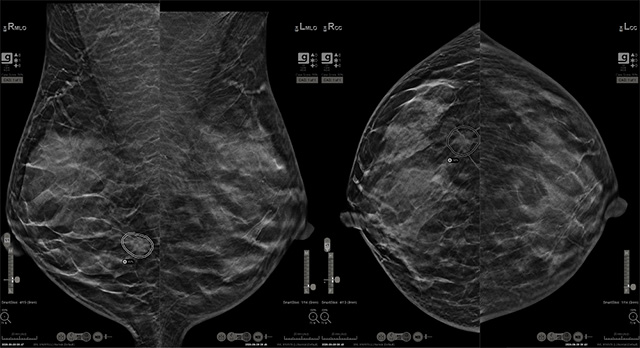

• 홀로직 유방암 AI 진단 보조 소프트웨어 Genius AI 2.0 /사진 제공=홀로직

▲ 홀로직 유방암 AI 진단 보조 소프트웨어 Genius AI 2.0 /사진 제공=홀로직

‘Genius AI Detection 2.0’은 홀로직의 3D 유방촬영장비와 연동돼 동작하는 인공지능 기반 솔루션으로, 3D 이미지를 기반으로 병변의 위치를 시각적으로 강조해 방사선 전문의의 판독을 보조한다. 홀로직 측에 따르면, 해당 기술은 미국에서 진행된 7,500건 이상의 임상 데이터 분석을 통해 다양한 연령과 인종에서 평균 민감도 94% 수준의 탐지 성능을 보였다고 한다.

영상 판독을 맡은 김수연 고대구로병원 영상의학과 교수는 “해당 사례는 무증상 상태에서 나타났고, 석회화 없이 비대칭 음영으로만 나타난 초기 단계의 병변이었다”며 “치밀 유방 특성상 명확한 식별이 어려웠지만, AI가 해당 부위를 강조함으로써 판독 시 주의 깊게 살펴볼 수 있었고, 그 결과 의심 소견을 확인할 수 있었다”고 설명했다.